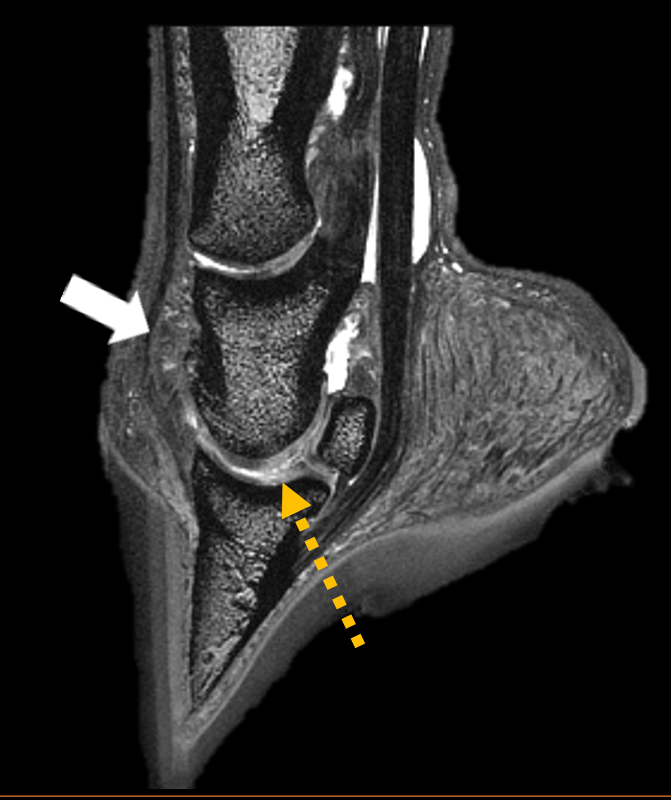

Professional reports with key images for all diagnostic imaging modalities, including radiographs, ultrasound, CT, MRI, nuclear scintigraphy.